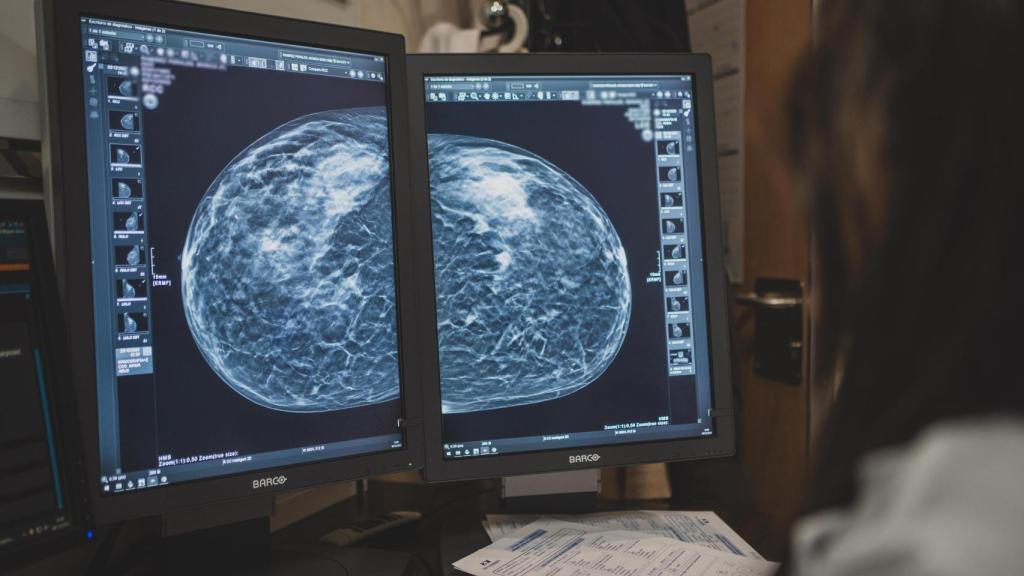

En el caso del cáncer de mama, el proceso que se sigue es el de hacer una mamografía. "Hay dos tipos de cribado: el poblacional y el oportunista. El sistema sanitario de España realiza el primero, cada dos años, y aquí —en referencia a HM Hospitales— hacemos el segundo", comenta la doctora Ana Delgado, especialista en radiología del HM Sanchinarro.

"Nosotros siempre aplicamos el mismo protocolo. En primer lugar, se hace una mamografía. En el caso de que haya una mama densa y heterogénea —aquella que tiene más tejido glandular y fibroso que graso. Implica mayor riesgo ante la posibilidad de padecer este cáncer—, se pasa a una ecografía, que es un proceso no invasivo", comenta la doctora Ana Delgado.

Tras esto, a medida que se va valorando el riesgo de la paciente, se aumentan las pruebas a las que debería someterse. La experta hace hincapié en la tomosíntesis digital una evolución de la mamografía convencional que crea una imagen casi tridimensional de la mama a partir de proyecciones 2D—.